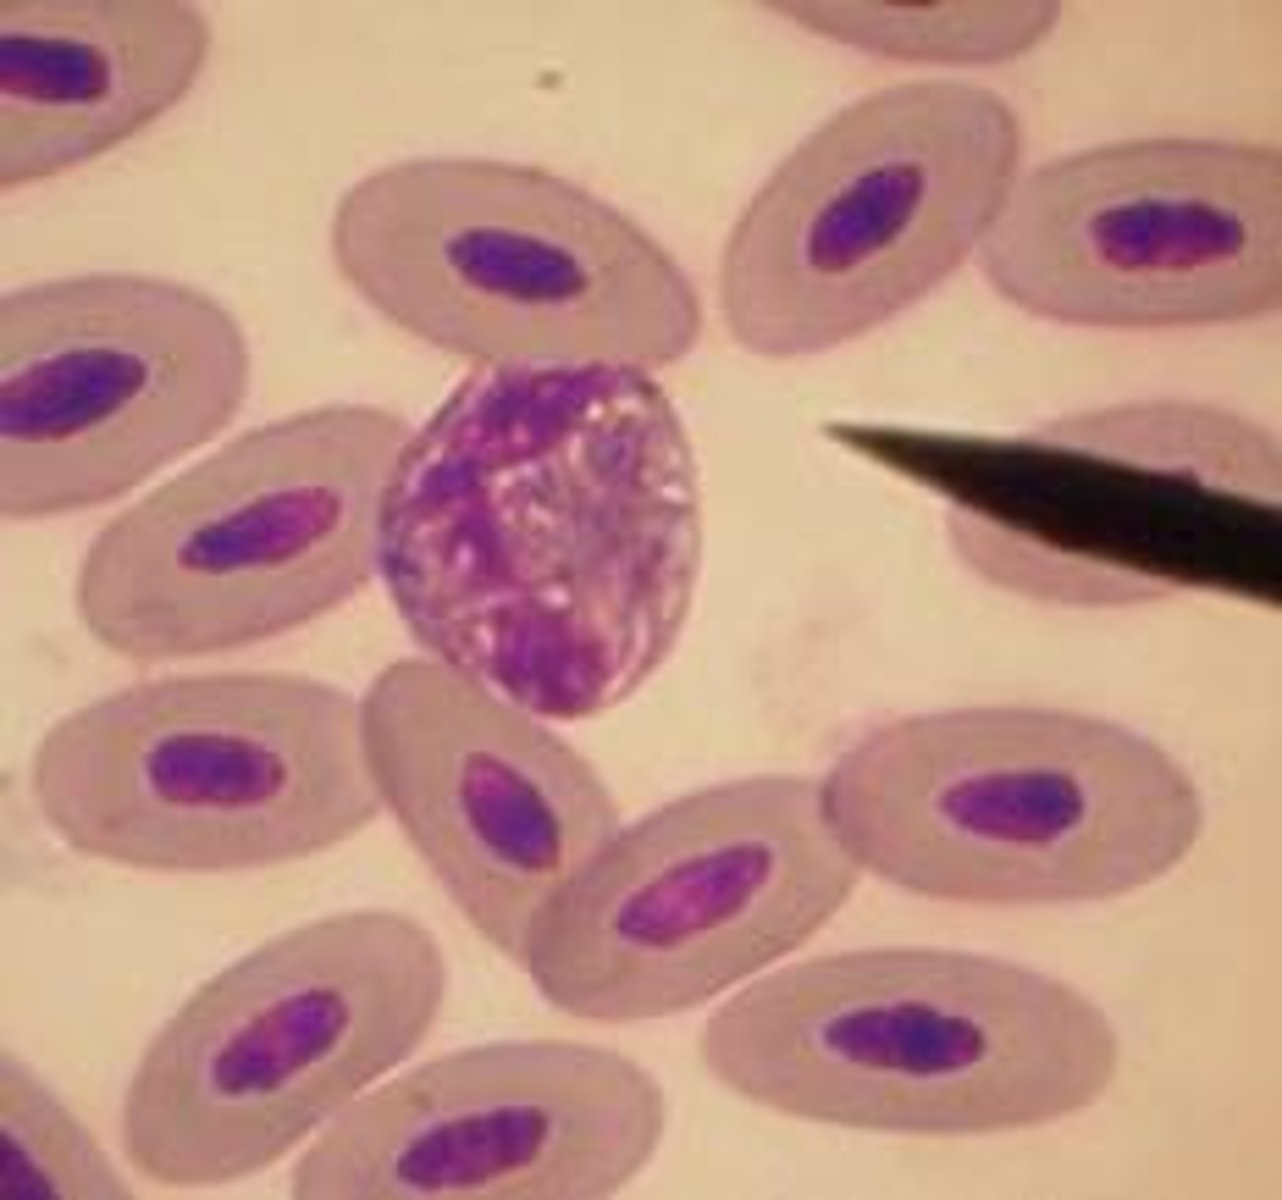

avian or reptile

organelle breakdown artifact on exotic RBC

exotic

hint: not clinically significant

degenerative organelle artifact on exotic RBC

exotic

small punctate, variably sized, clear vacuoles that are not clinically significant

exotic polychromatophils

exotic

slightly rounder

basophilic cytoplasm